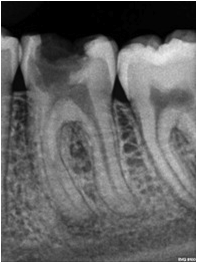

Fotos de casos clínicos